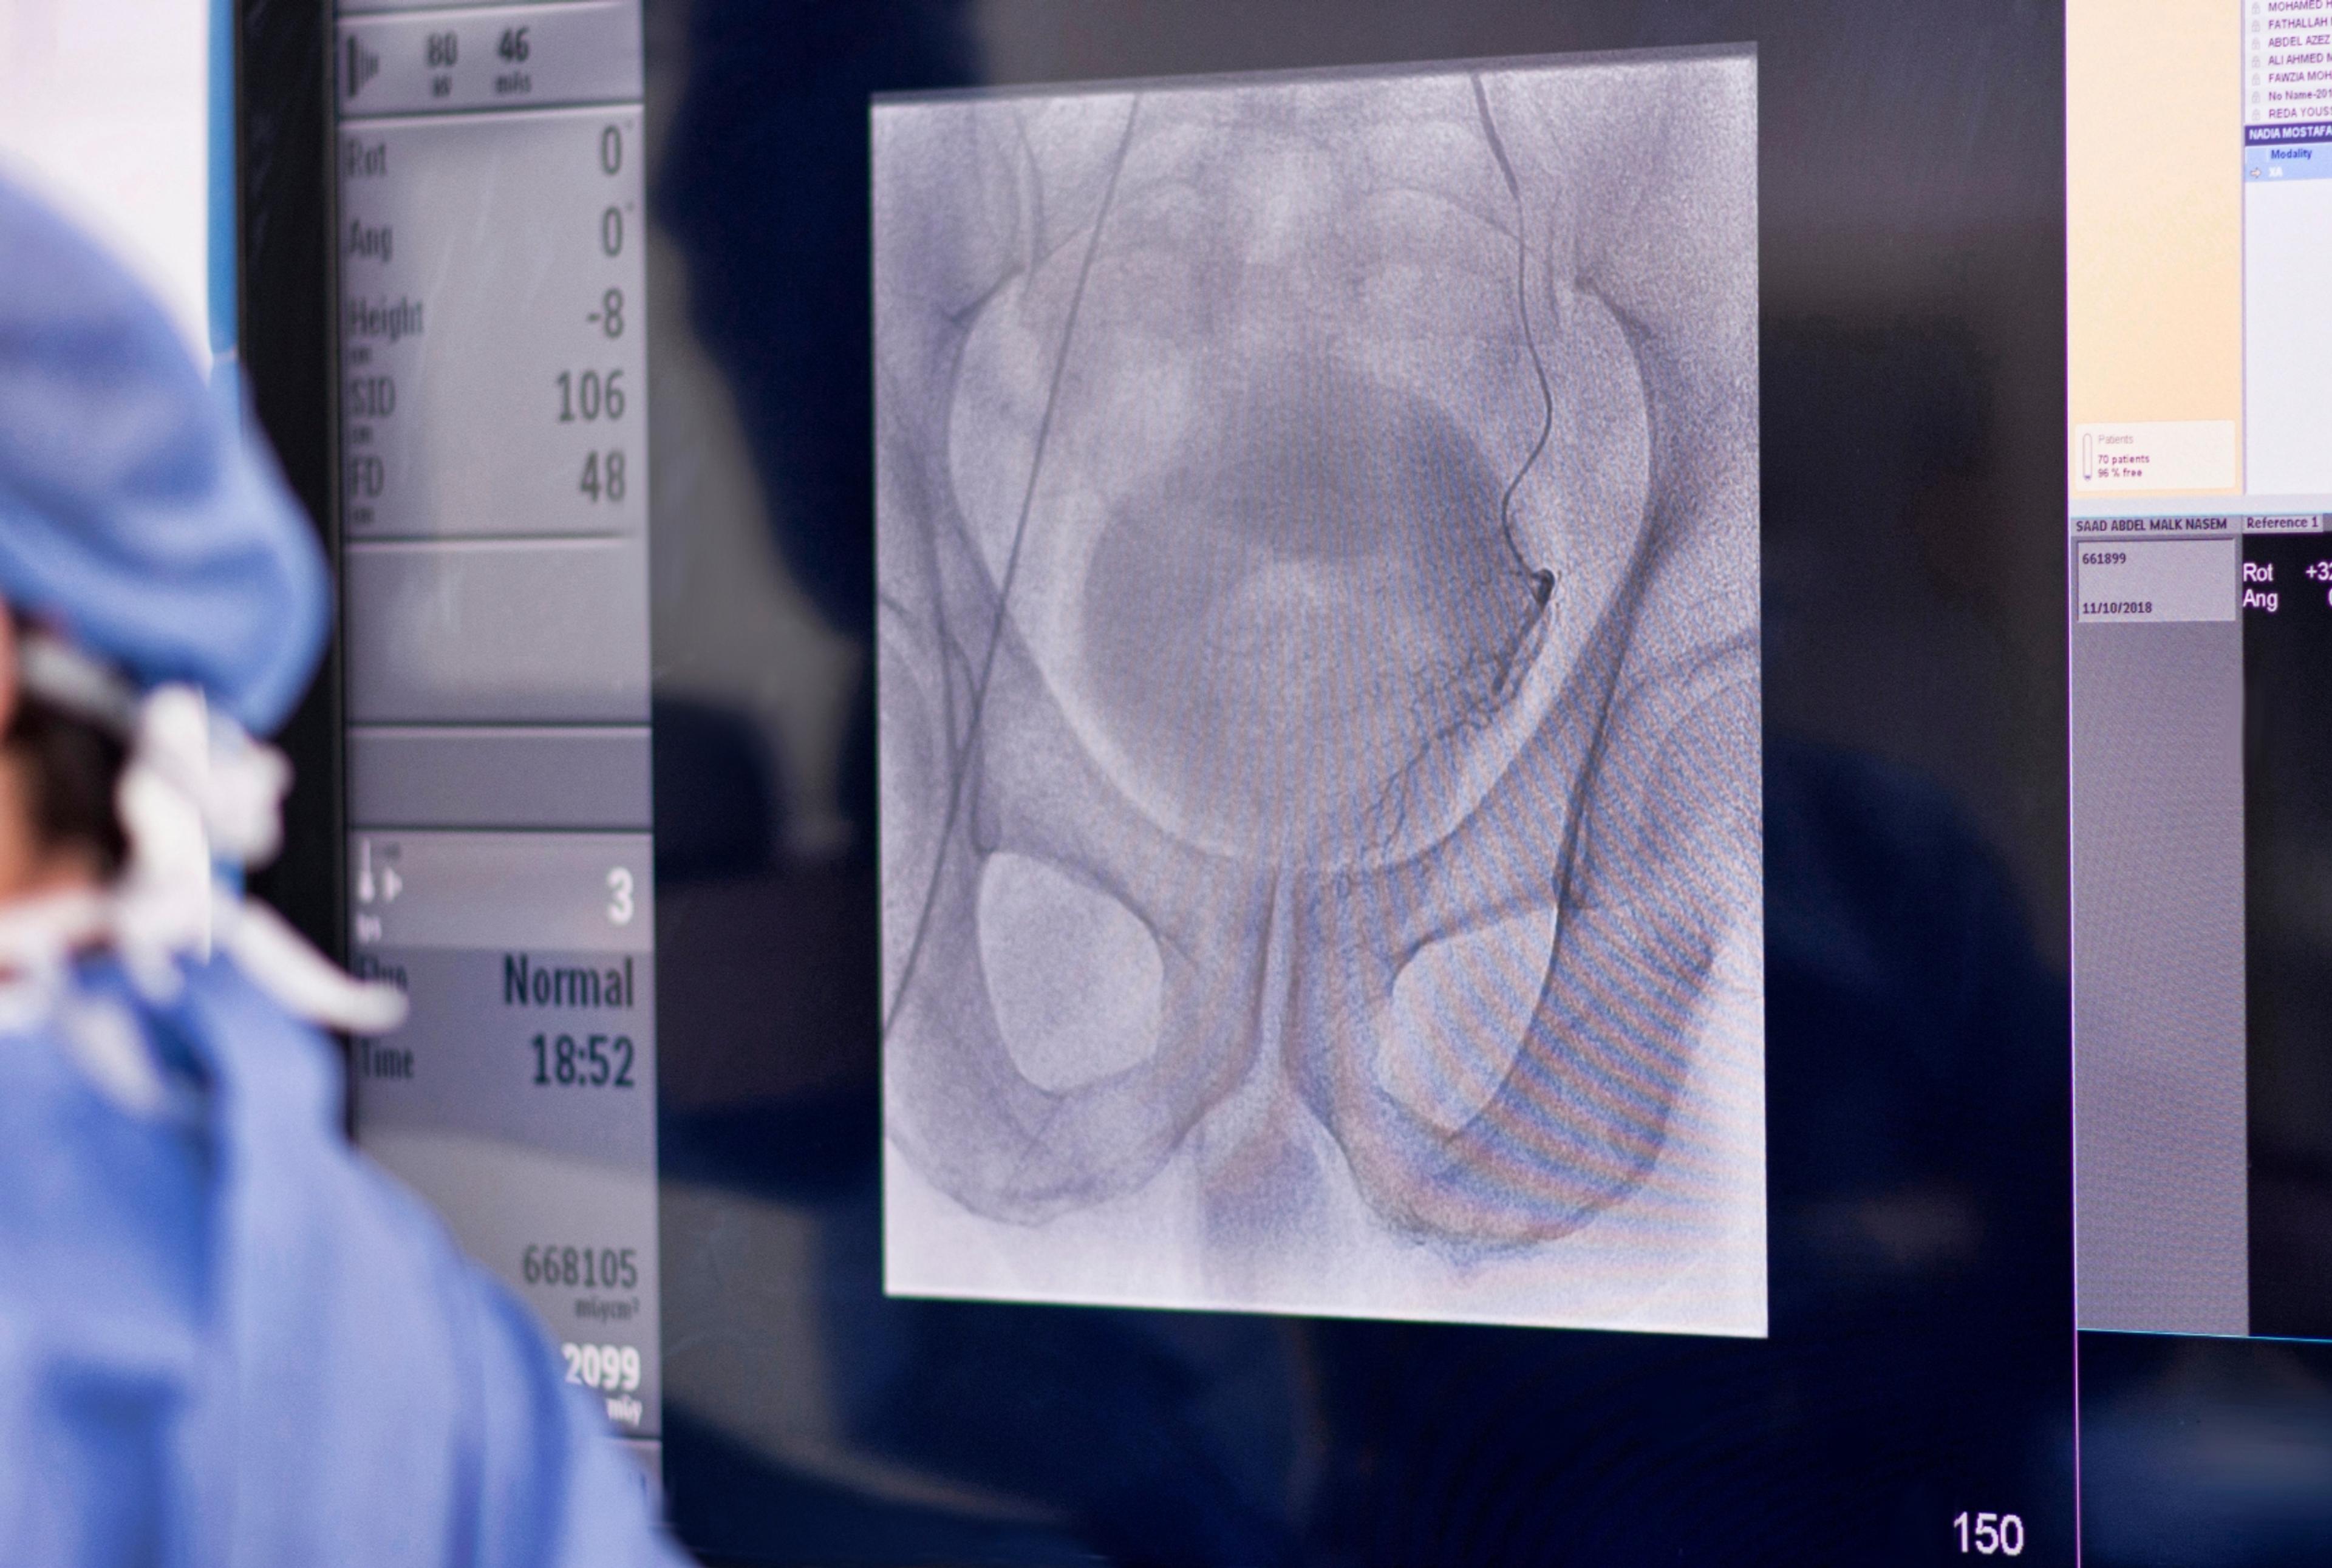

Detachable coil embolization treats aneurysms and other blood vessel malformations in the brain and other parts of the body, alleviating much of the danger presented by aneurysms. A catheter is inserted into an artery in the leg then maneuvered through the body to the aneurysm's position. Soft detachable coils are inserted through the catheter into the aneurysm. The body responds by forming a blood clot around the coil blocking off the aneurysm. Coils can be used either to block blood flow to the affected area or to fill the aneurysm or fistula, thus preventing a rupture. This procedure is effective in prolonging life and relieving symptoms.

Chemoembolization combines chemotherapy and the embolization procedure to treat cancer, primarily in the liver. Embolization is a treatment in which blood vessels or malformations within blood vessels are blocked off. In chemoembolization, the anti-cancer drugs are injected directly into a cancerous tumor while an embolic agent is used to maintain the chemotherapy within the tumor which helps to prolong the effect of the chemotherapy agent.